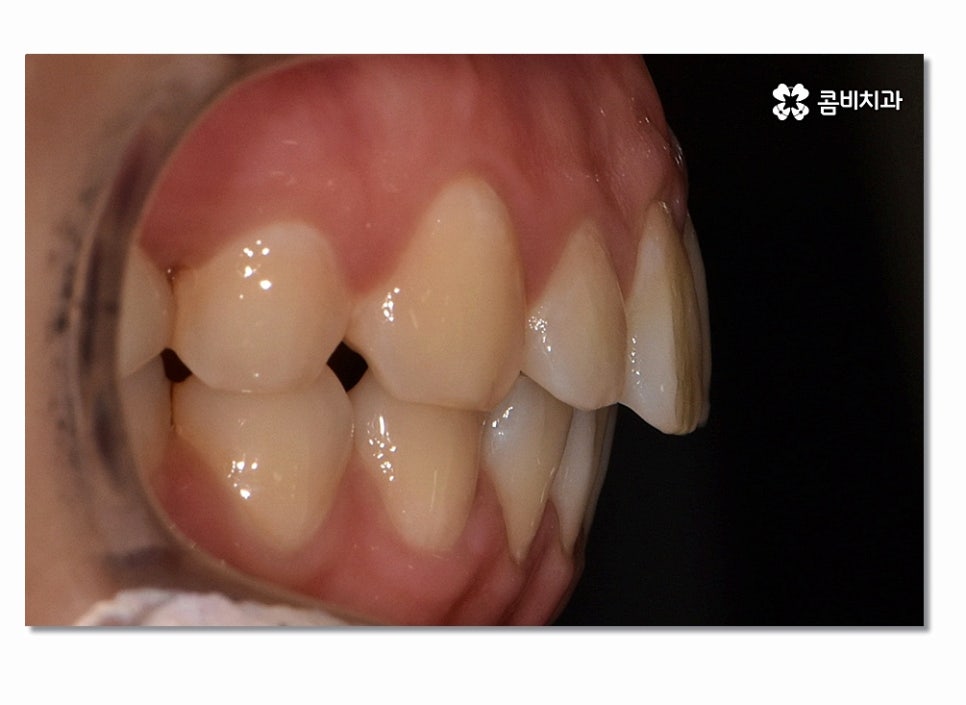

돌출입은 치아 자체가 앞으로 뻐드러진 경우와

치아, 잇몸이 모두 돌출된 경우로 구분하게 되는데 오늘은

전자의 경우로 발치를 통해 돌출입치아교정이 이뤄진

케이스에 대해서 소개 드릴 거예요.

돌출입치아교정이 시작되면 이처럼 전방으로 뻐드러진

앞니를 시간이 지남에 따라서 후방으로 이동시키면서 돌출입이

점점 개선되며 이러한 치열의 변화는 교합도 잘 맞물리도록

위 사진을 보시면 치아교정 과정을 통해서 치열의 가지런함은 물론이며

측면에서 보더라도 돌출입이 많이 개선된 것을 느낄 수 있을 거예요.